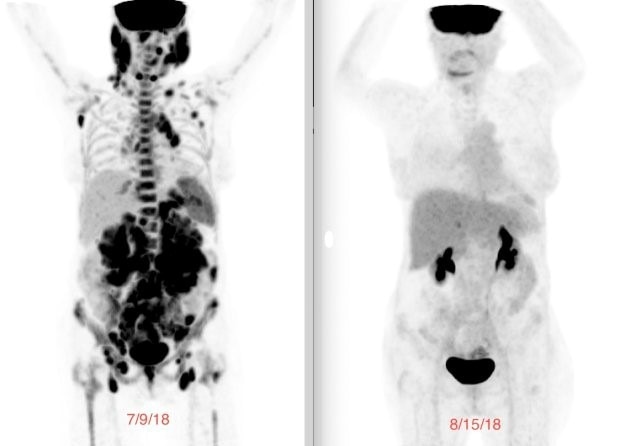

A week before the infusion, my baseline PET scan showed tumors lighting up throughout my body. Just 29 days later, the follow-up scan showed no evidence of disease. I was finally in complete remission. No one could believe it. It was astonishing how quickly and effectively it worked.

Laurie's PET scan before CART T-cell therapy (left) and after (right).